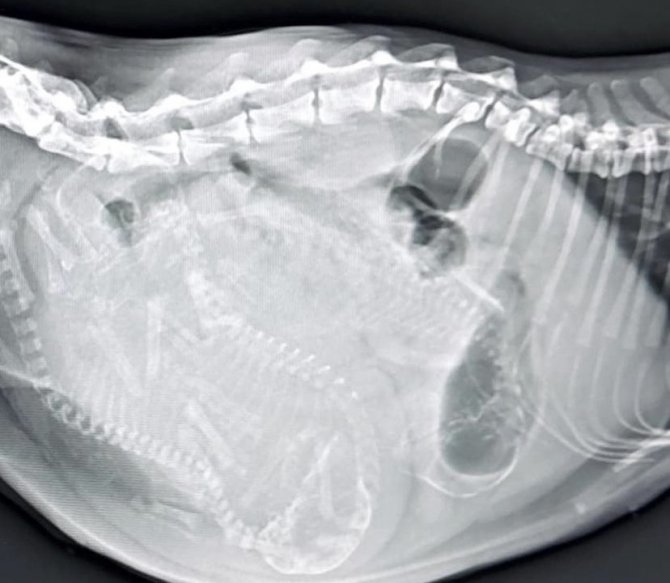

Zonguldak'ta 1 yaşındaki tekir cinsi kedi doğum yapamama nedeniyle kent merkezinde ki özel veteriner kliniğe getirildi. Veteriner hekim Gökmen Koç tarafından muayene edilen kedinin rahiminden yavruların sıkıştığı tespit edildi. Ardından sezaryenle ameliyatla alınan anne kedinin rahiminde sıkışan 3 yavru çıkartıldı. Ancak yavruların sezaryenle çıkartılması nedeniyle bu kez de anne kedi yavruları kabul etmedi. Hayvan sahipleri 6 gün boyunca yavruları anne kediye yaklaştırarak emzirmesini sağladı. 6 günün sonunda anne kedi yavrularını kabul etmesiyle problem çözüldü.

Veteriner Hekim Önder Koç, "Pazar sabahı kedimden akıntı geldi. Dışarı da kuyruğunu görüyoruz ama çok fazla ıkınıyor ağrısı acısı var. Doğumunu gerçekleştirmiyor. Yapılan tetkik ve ultrasonda kedimizin doğuramadığını ve kanala sıkıştığını tespit ettik. O yüzden ameliyat kararı verdik. O ilk sıkışan yavru gerçekten çok büyüktü. Kesinlikle kanaldan geçecek ebatlarda değildi. Rahminden çıkardık yavruları. Kızanın etkisi ile dışarıda hangi kedilerle çiftleşti bilinmiyor. Cüsseli bir erkek kesiyle çiftleşmiş haddinden büyüktü yavrular. Ardından da kapattık. İlk 5 gün anne kedi sezaryenle doğum yapıldığı için anne kedi yavrularını kabul etmedi. Hasta sahiplerini yavruları tutarsak anneye getirdi. 2 saatte bir böyle beslemeler yaptı. Annenin altında sıcaklığını korudu. Yeri geldi yavruların üzerlerini sürttürerek sıcaklıklarını anneye geçirtti. Şu anda 6'ıncı günün sonunda çok şükür anne yavrularını kabul etti ve beslemeye başladı. Annelik içgüdüsünü kazanmış hale geldi. Şu anda problem yok" dedi.